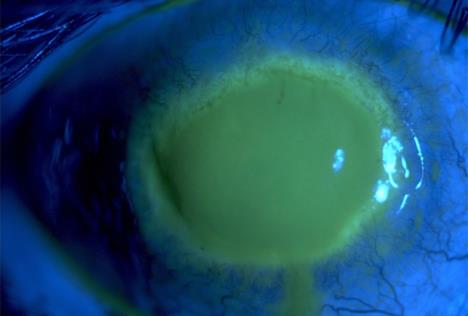

"Do kraja nedelje, oko mi je nateklo i izgledalo je kao velika crvena loptica za golf", priča Džesika. Bol je postala neizdrživa, pa su je 26. marta primili u bolnicu. Ispostavilo se da joj je oko napala je bakterija Acanthamoeba Keratiti, Ona je inače normalan stanovnik tla i voda i bila je u onoj kapljici česmovače što je prsnula na Džesikino sočivo, ali zaglavila se između sočiva i oka, pa je počela da progriza put kroz njeno oko...

acanthamoeba-keratitis.jpg

Foto: Wikimedia Commons

"Parazit mi je i dalje izjedao oko, a što je još gore, imunološki sistem mi je padao zbog nedostatka sna", prepričava Džesika. I kad su je otpustili iz bolnice, morala je da nastavi svakog dana da ukapava po 21 kap dok crvenilo i oko ne spadnu.